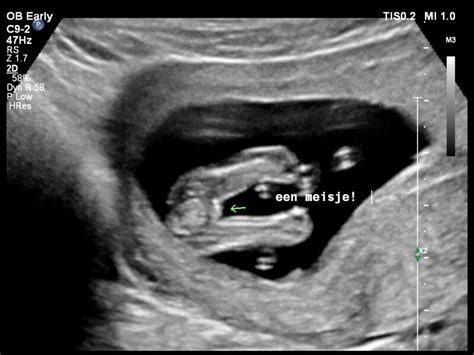

De meest voorkomende en betrouwbare methode om het geslacht van de baby te bepalen, is de echografie. Rond de 16 weken zwangerschap kan het geslacht met redelijke zekerheid worden vastgesteld. De baby is dan ongeveer 15 cm lang en weegt 100 gram. Het is belangrijk te weten dat het geslacht niet altijd direct goed zichtbaar is; de positie van de baby, of de beentjes voor het geslachtsdeel zitten, kan de zichtbaarheid beïnvloeden.

De 20-weken echo, ook wel de morfologische echo genoemd, is een standaardonderzoek waarbij de anatomische kenmerken van de baby uitgebreid worden bekeken. Tijdens deze echo kan de echoscopist het geslacht van je baby bepalen, mits de baby in een gunstige positie ligt. Duidelijk zichtbare kenmerken bij een meisje zijn de schaamlippen en clitoris, die eruitzien als twee kleine lijntjes of ovaaltjes. Bij een jongen zijn de penis en het scrotum duidelijk zichtbaar als een uitstekend deel.